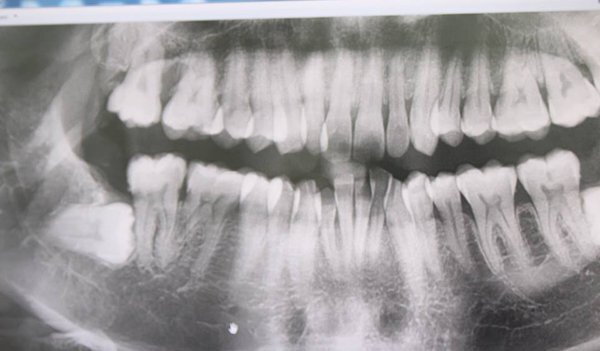

mọc răng số 8 hàm dưới bên trái

Răng khôn đâm thủng má, cô gái trẻ phải bỏ thai

BS buộc phải đình chỉ thai để điều trị kháng sinh do răng khôn áp xe nặng, tạo ổ mủ, thủng má.